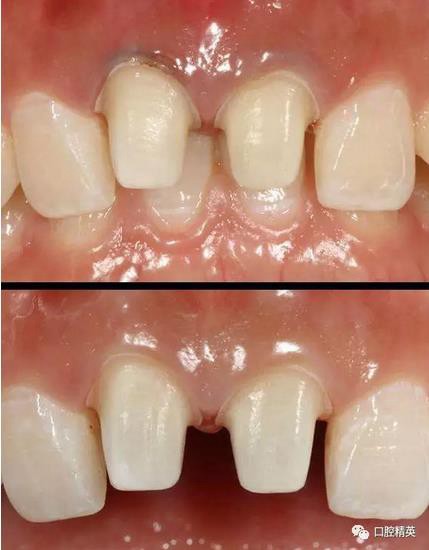

修復體戴入

口內(nèi)正側(cè)位及切端特寫

從側(cè)位照可看出遠中切角略有回收

術前,術中,術后對比

對比來看基本達到患者預期

有一點不足之處在于齦緣的高低不完全一致,補救辦法同上——激光輕掃